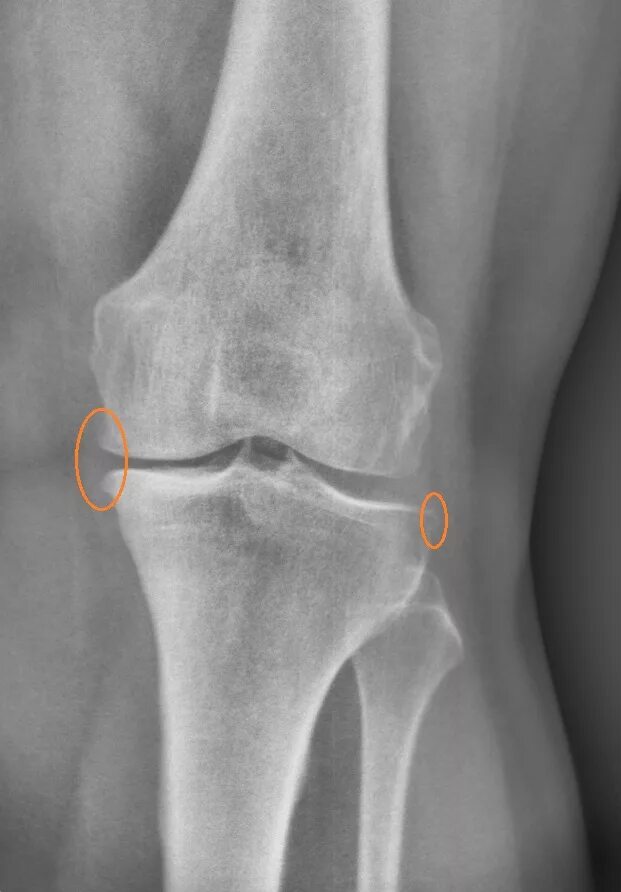

Суставная мышь коленного сустава. внутрисуставная мышь коленного сустава. сужение суставной щели.

Остеоартроз коленного сустава рентген. гонартроз коленного сустава 1. гонартроз коленного сустава рентген. деформирующий гонартроз рентген.

Остеоартроз коленного сустава рентген. рентген коленного сустава деформирующий гонартроз. деформирующий артроз коленного сустава рентген степени. рентген колена деформирующий артроз.

Деформирующий остеоартроз рентген. рентген коленного сустава деформирующий гонартроз. остеоартроз коленного сустава рентген. деформирующий артроз коленного сустава рентген.

Гонартроз 2 степени рентген. гонартроз 1 степени на рентгене. деформирующий остеоартроз коленного сустава рентген. гонартроз коленного сустава 1 степени на рентгене.

Остеофиты коленного сустава рентген. субхондральный остеосклероз рентген. остеосклероз коленного сустава рентген. рентген остеосклероз костной ткани.

Деформирующий артроз суставная щель коленного сустава. субхондральный отдел большеберцовой кости. остеосклероз коленного сустава рентген. артроз коленного сустава суставная щель сужена.